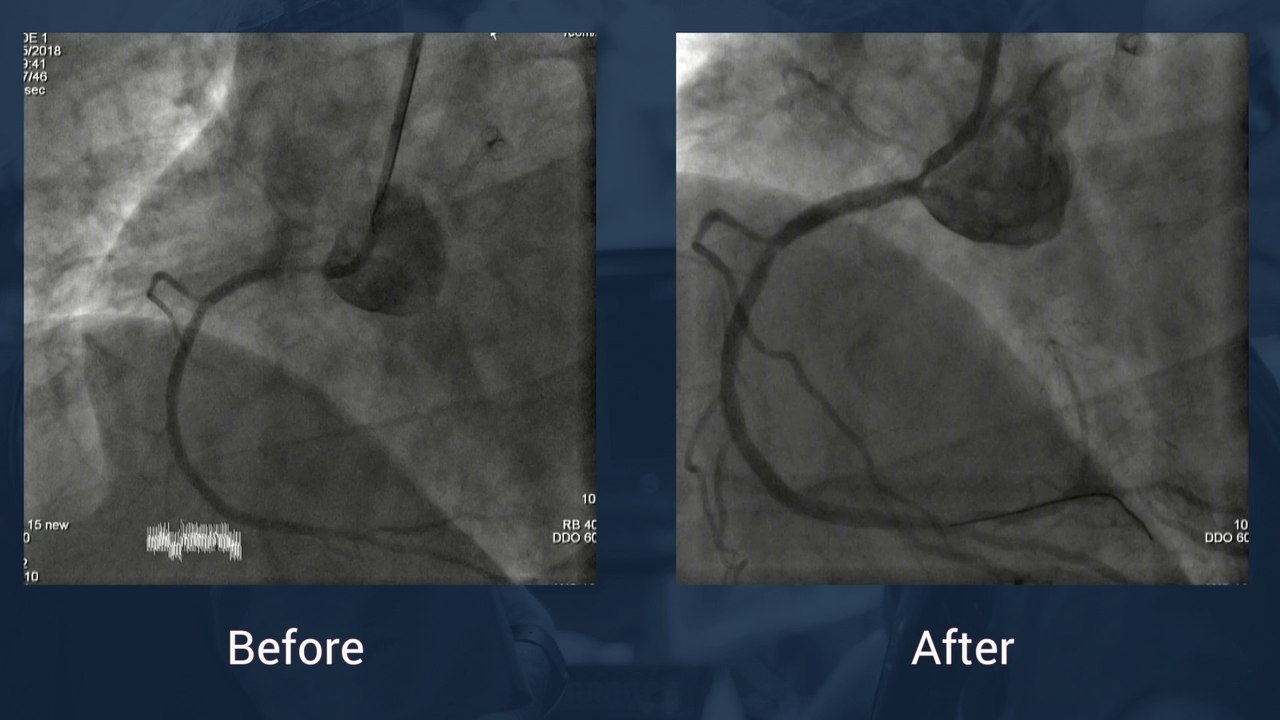

La coronaire à la parisienne : de l'aigüe au chronique